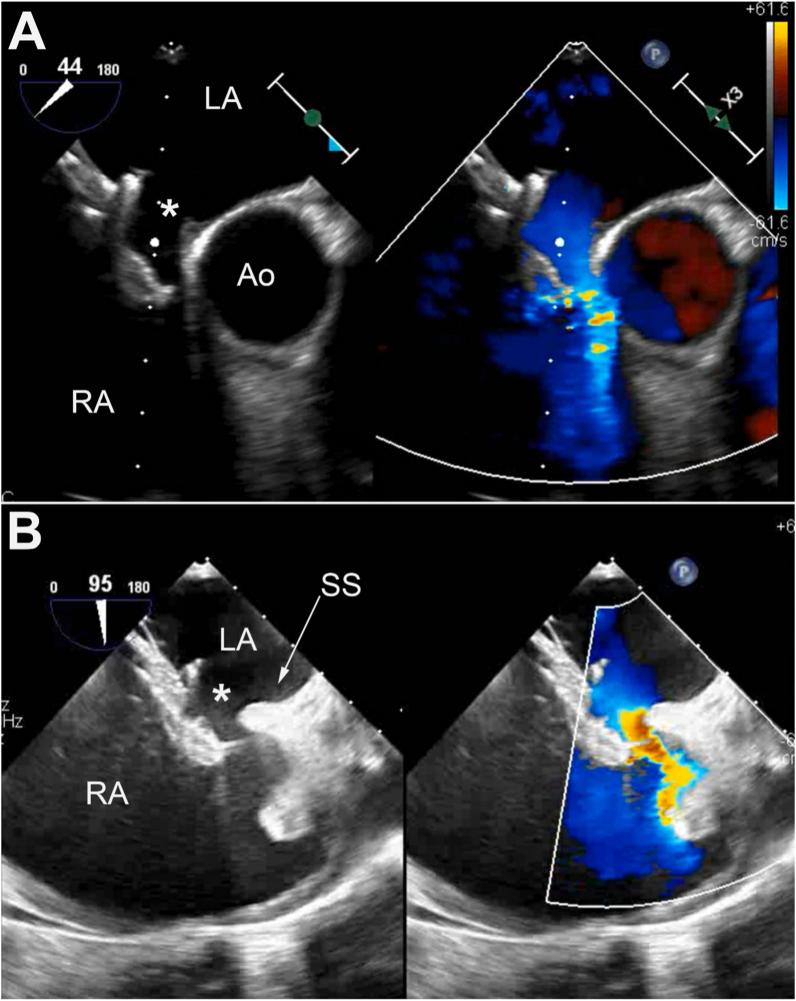

Percutaneous closure of ASD is nowadays preferred and more widely performed over surgical closure. The GORE® CARDIOFORM ASD occluder (GCA) is the latest generation of occluder with promising results as it performed well with high successful implant rates (96%) and showed high efficacy in challenging clinical and anatomical situations. We present the case of a 65 female with a 2.5 cm ASD, left atrial hypertension, deficient retroaortic rim, mobile septum primum and hypertrophied septum secundum. She underwent uncomplicated closure with a 44-mm GCA. However, the patient presented to the emergency room five weeks post procedure and was found to be in atrial fibrillation with rapid ventricular response at a rate of 158 bpm. Further workup showed a dislodged GCA device despite appropriate device placement and size selection based on the published instructions for use. We elected to not remove the 44-mm GCA given that it had become adherent to the septum primum but instead used the stiffer Amplatzer septal occluder to stabilize the GCA and occlude the residual defect. Finally, we highly recommend taking device destabilizing factors into consideration when selecting device size.

如今,经皮封堵房间隔缺损(ASD)比外科手术封堵更受青睐且应用更为广泛。戈尔公司的CARDIOFORM ASD封堵器(GCA)是新一代封堵器,取得了令人瞩目的成果,其植入成功率高(96%),在具有挑战性的临床和解剖情况下也显示出高效性。我们报告了一例65岁女性患者,患有2.5厘米的房间隔缺损、左心房高压、主动脉后缘不足、原发隔活动及继发隔肥厚。她使用44毫米的GCA进行了顺利封堵。然而,患者在术后五周因快速心室反应性房颤(心率158次/分钟)就诊于急诊室。进一步检查发现,尽管根据已发布的使用说明进行了合适的装置放置和尺寸选择,但GCA装置仍发生了移位。鉴于44毫米的GCA已与原发隔粘连,我们选择不取出它,而是使用更硬的Amplatzer房间隔封堵器来稳定GCA并封堵残余缺损。最后,我们强烈建议在选择装置尺寸时考虑装置不稳定因素。